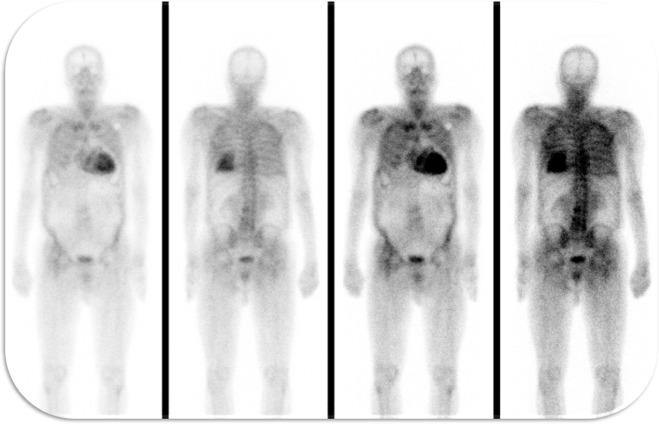

第二年,他患上了NYHA II至III级充血性心力衰竭(HF),需要增加利尿剂的用量。重复超声心动图显示中度向心性左心室肥厚,射血分数保留,但整体纵向应变异常和充盈压力升高。患者复查了冠状动脉造影,排除了冠心病进展。又接受了99mTc-DPD显像检查,显示明显的心肌示踪剂摄取,诊断为TTR淀粉样浸润。(图1)经药物治疗后病情稳定,并持续密切随访,对劳力性微血管心绞痛需进行抗心绞痛提升治疗。

图1、99mTc-DPD显像显示心肌示踪明显,诊断TTR淀粉样浸润